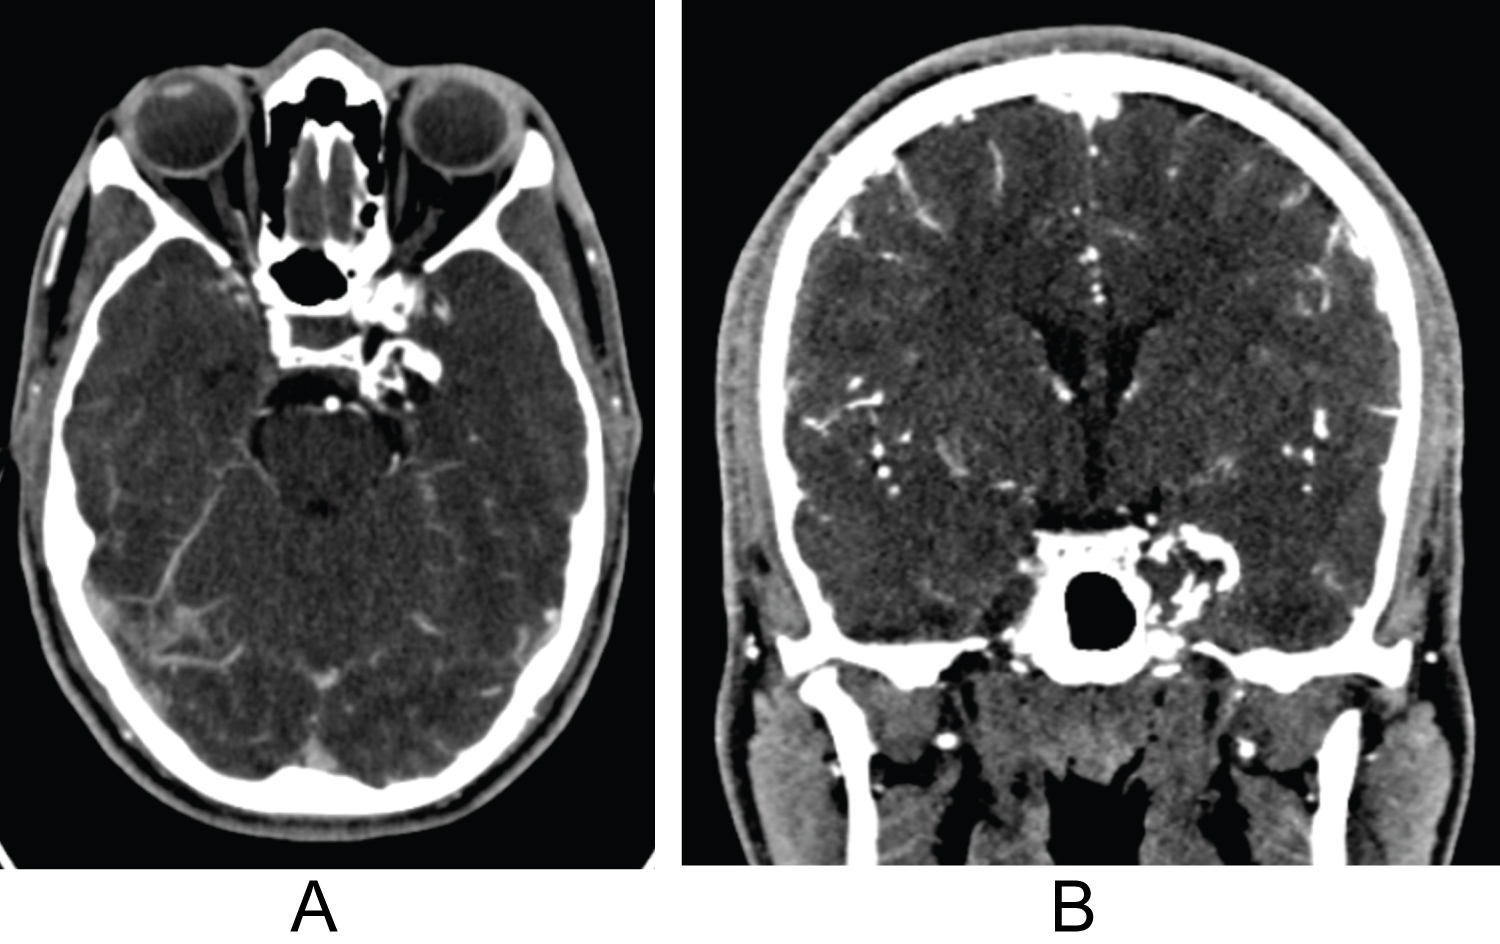

During the three month follow up visit, there was residual diplopia and decreased sensation upper part of left forehead (V1 distribution). At the 12-month follow up visit, the patient reported persistent but much improved CN VI palsy with intermittent conjunctival irritation and persistent decreased sensation at left cranial nerve V1 distribution. 12-month post-op MRI noted improved decompression of the cavernous sinus and residual postoperative enhancement along left petroclinoid ligament with extension toward the cavernous sinus (Figure 3A and Figure 3B).

Figure 3: (A,B) 12 months post-operative axial and coronal brain MRI imaging using T1 sequence with contrast shows gross total resection of the cavernous sinus mass with improved mass effect on mesial temporal lobe and ICA artery. View Figure 3